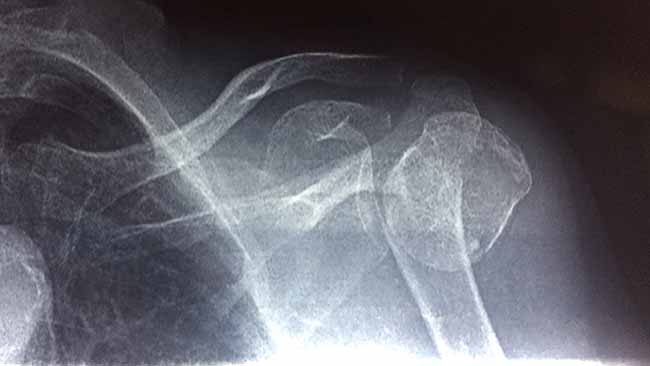

The next time she came in, she removed her sweater. Her humerus bone jutted up through her skin every time she moved her arm. We looked at all the info she had. A couple of months previous, she had fallen with her arm out to the side. She’d broken the bone at the elbow and the shoulder. The humeral head had actually split in half.

I still look at the films a lot and I even now, can’t tell if the spine of the scapula and glenoid cavity was broken as well. There is no complete x-ray series here. Nepal operates on a ‘get what you get and don’t throw a fit’ imaging policy.